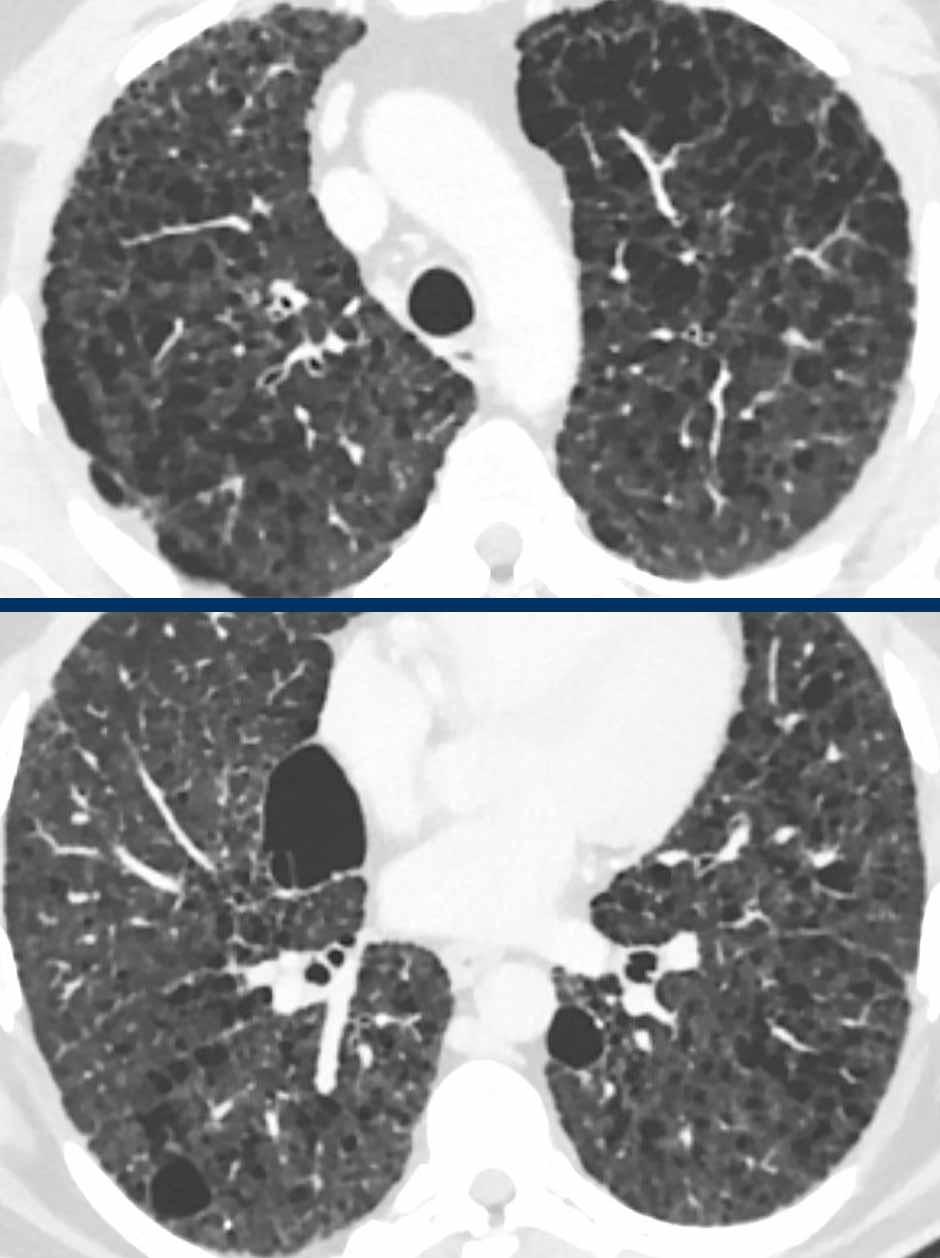

Đây là hình ảnh của hai bệnh nhân khác nhau.

Hãy phân tích hình ảnh.

Nhận xét hình ảnh

Mặc dù thoạt nhìn hai hình ảnh này trông có vẻ tương tự nhau, có thể nhận thấy rằng ở bên trái là các nang thực sự có thành trong một bệnh nhân LCH giai đoạn tiến triển, trong khi ở bên phải một số tổn thương có vẻ có thành nhưng phần lớn thì không.

Đây là hình ảnh khí phế thũng trung tiểu thùy.